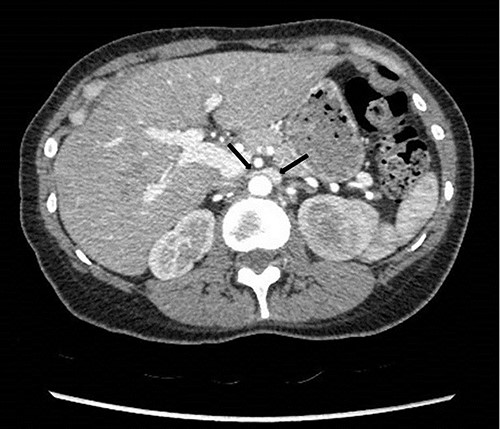

To investigate the bleeding source, she subsequently had a CT renal angiogram 3 days later that showed a narrow angle between origin of SMA and the aorta (Fig. 3) with multifocal areas of hypoattenuation throughout the left renal cortex (Fig. 4). It showed a compression ratio of 3.25 (diameter of pre-compressed vein =6.5 mm; diameter of compressed vein =2 mm) (Fig. 5).

Computed tomography angiogram on presentation showing pre-compressed LRV (right arrow); and compressed LRV (left arrow).

Computed tomography angiogram 6 months later showing pre-compressed LRV (right arrow); and compressed LRV (left arrow), but resolution of the congestion and swelling of the left kidney.